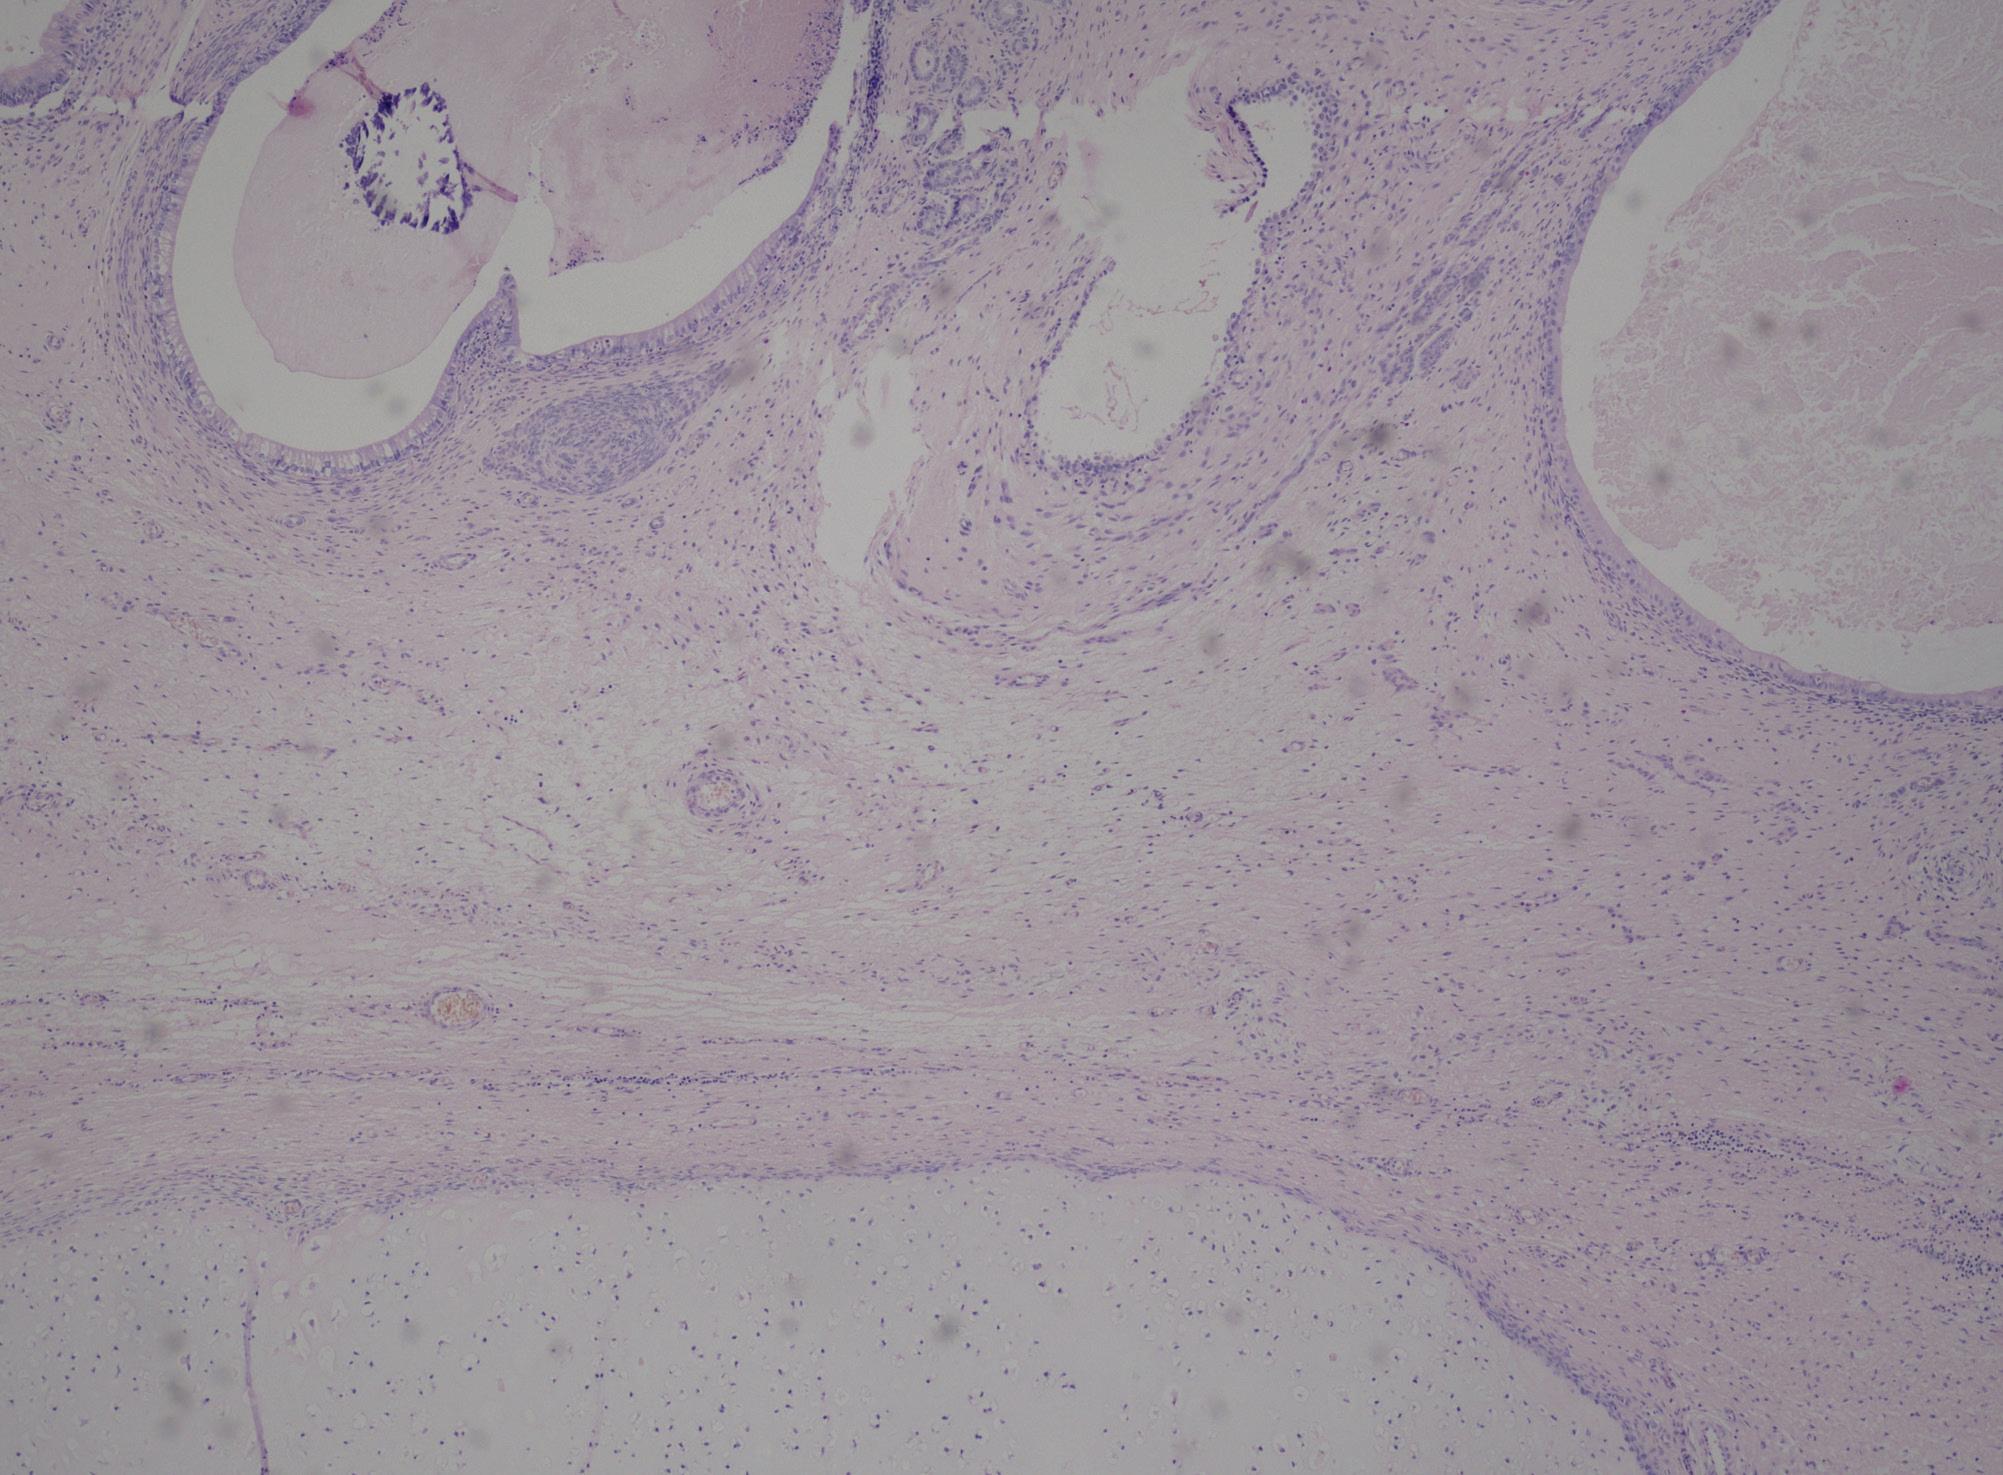

Materiál pro histologické vyšetření byl zpracován dle klasického schématu, fixován ve 4% roztoku formaldehydu

a zalitý parafínem. Z parafínových bločků byly na mikrotomu krájeny řezy tloušťky 1–2 µm a tyto obarveny v hematoxylinu a  eozinu. Histologická klasifikace bioptického materiálu byla provedena v souladu se Světovou zdravotnickou organizací (WHO – World Health Organisation) 2016/2022 a současně i s WHO 1973 dle doporučení EAU.